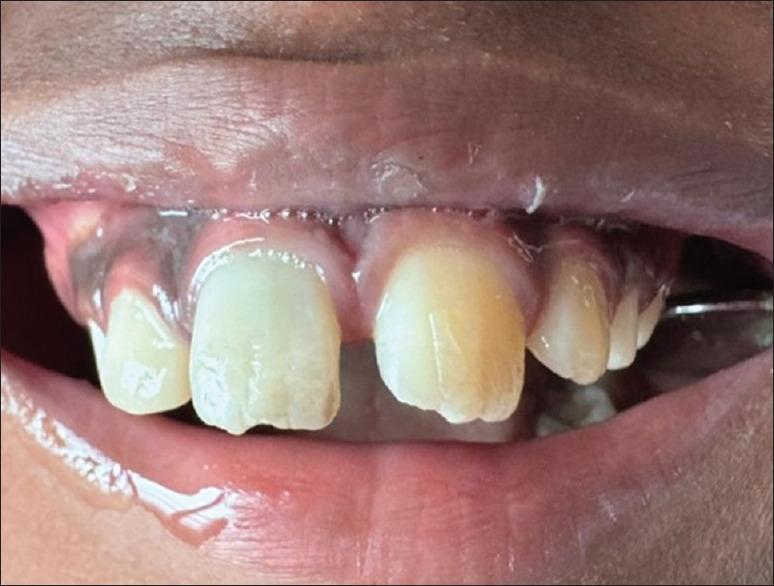

Successful re-plantation of avulsed tooth in children demands instantaneous management. This case report emphasizes the efficient treatment of a 09-Year-old boy who suffered an avulsion of the maxillary right central incisor at his school. The patient reported within half an hour of the traumatic dental injury with the avulsed tooth in his hand wrapped in a piece of newspaper. Immediately the tooth was placed in normal saline (0.7%) when the patient arrived and conventional Root Canal Therapy (RCT) was done extra-orally. After the root canal, the tooth was re-planted according to the IADT guidelines and stabilized in place with splinting. Our interpretation suggests that re-plantation of an avulsed tooth as quickly as possible, using appropriate splint and planned root canal therapy, promotes faster periapical healing and yields a better prognosis.